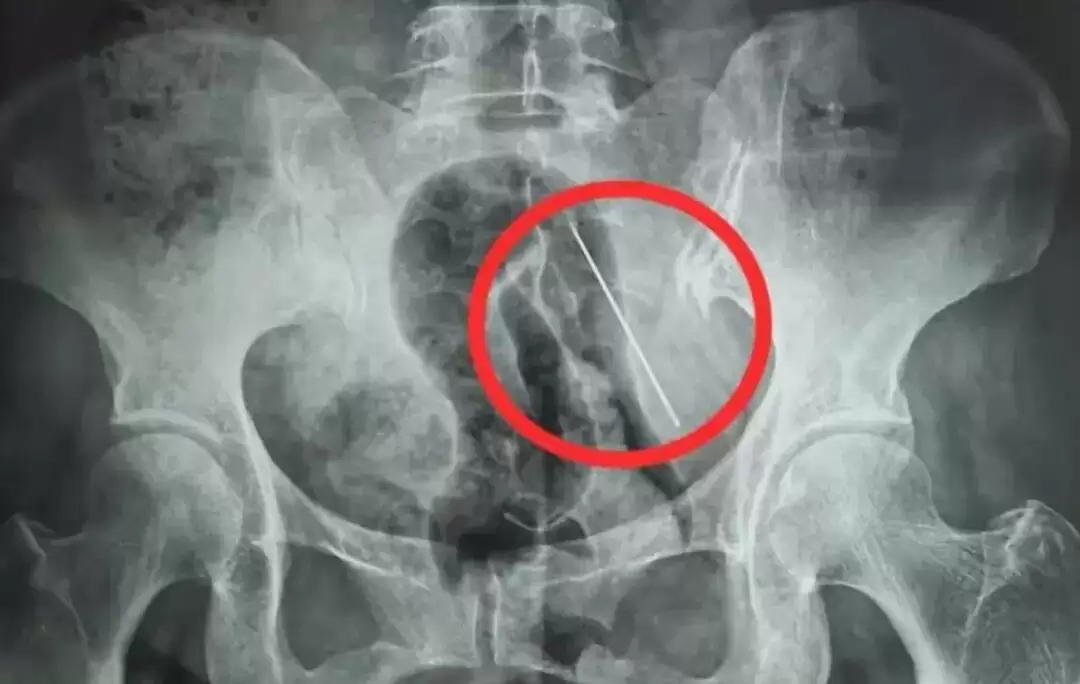

X光片显示张某腹部内有异物(医院供图)

接诊后,急诊科当即安排张某进行腹部CT和X线检查。检查后果显示,她的腹壁内有一根长4厘米的异物。经研判,这根缝衣针只是扎入脂肪层内,并未穿透掉入腹腔。